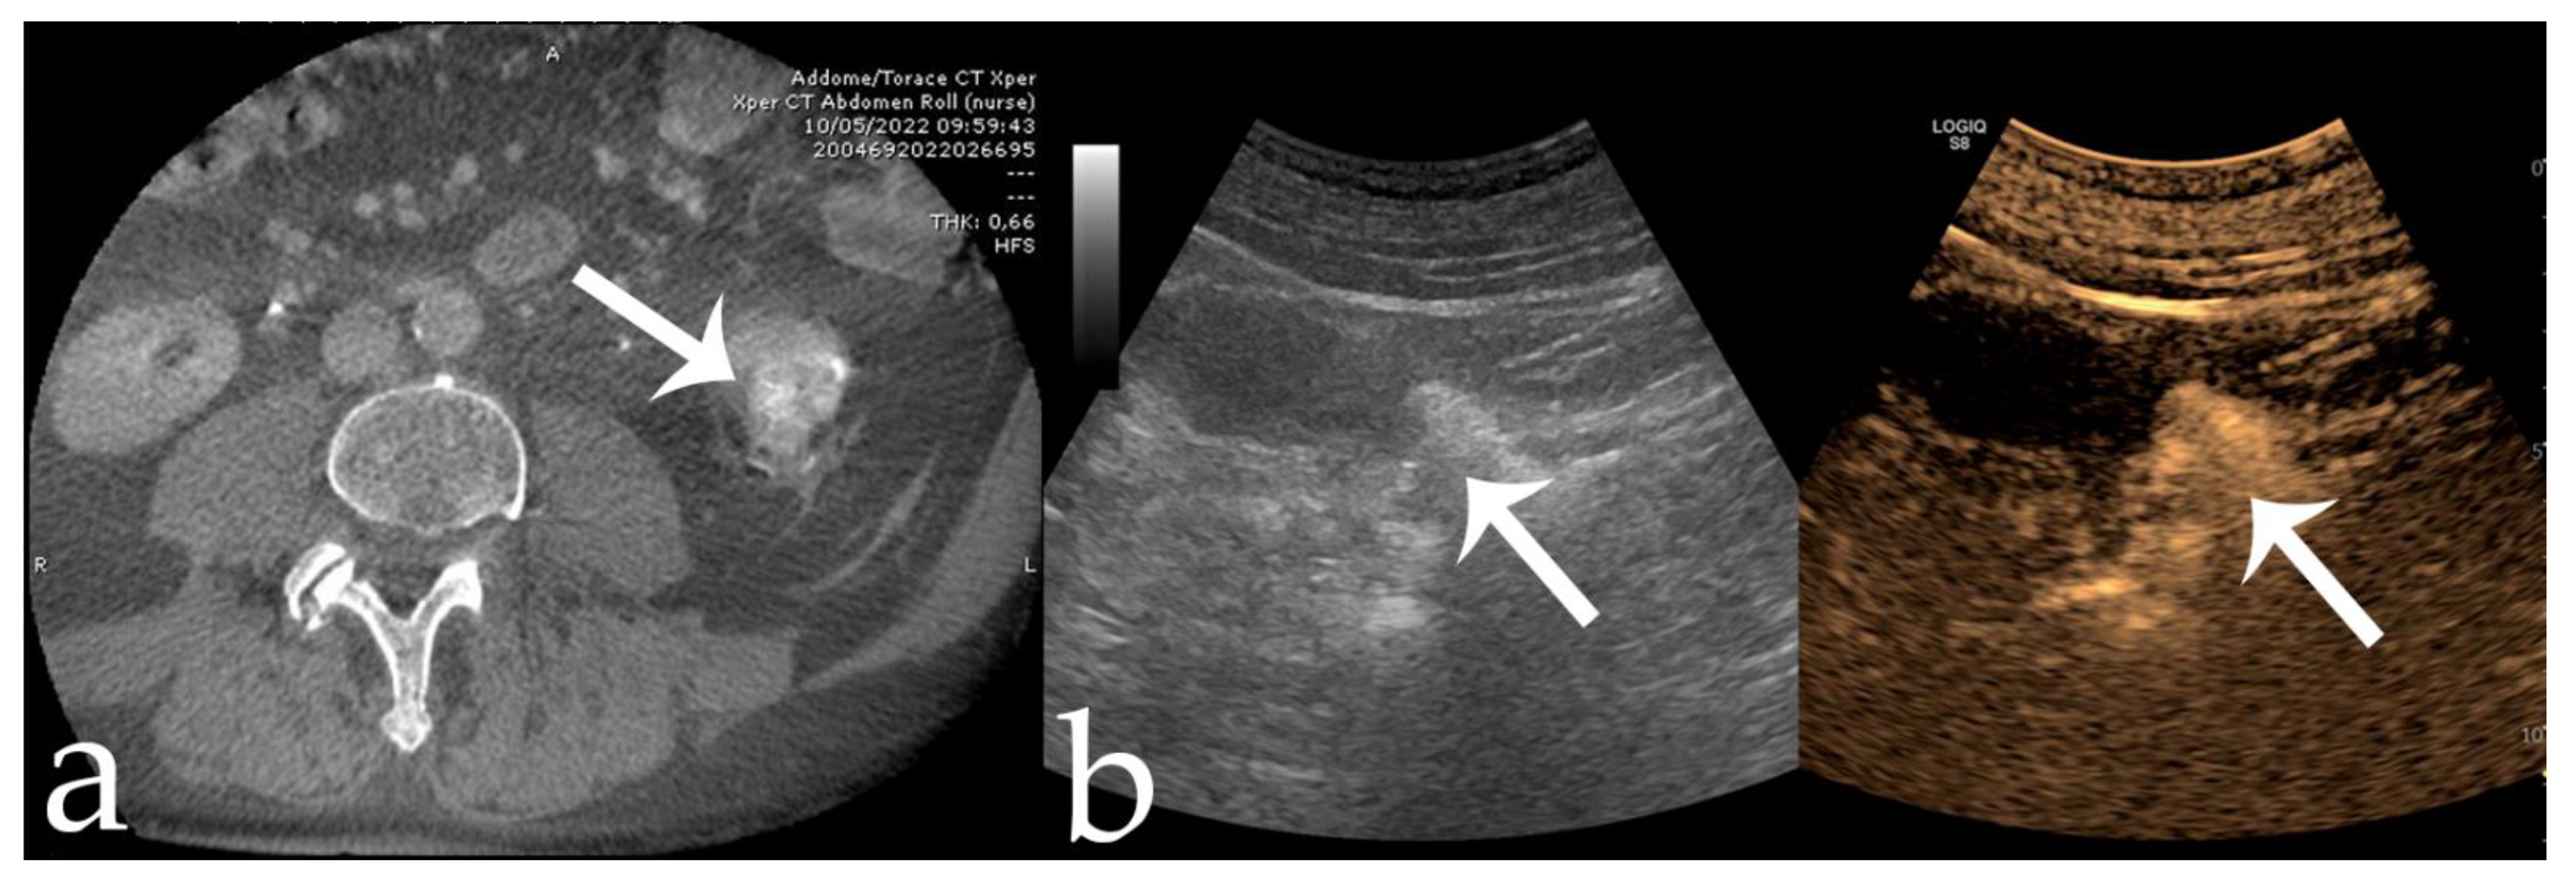

Figure 4. Same case as Figure 3. (a,b) Post-procedural CBCT and CEUS showing complete tumor devascularization (arrows).